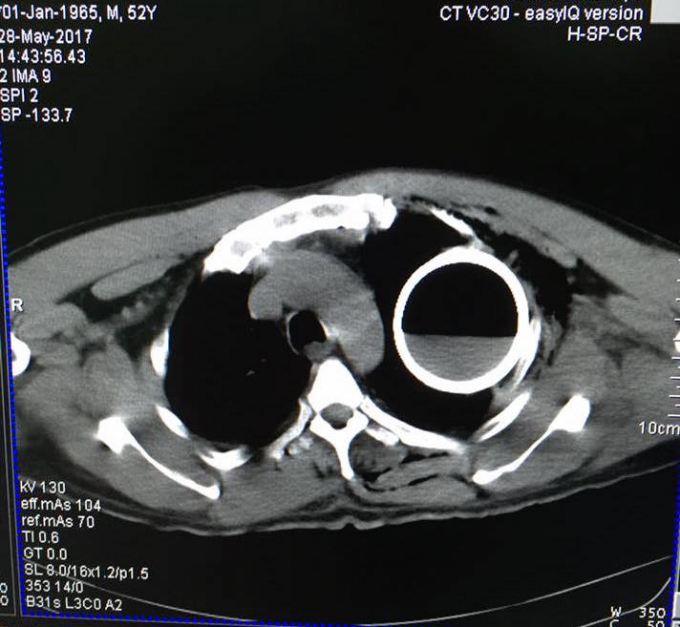

Sau khi các bác sĩ chỉ định chụp X-Quang cho bệnh nhân và hoảng hốt khi phát hiện trong vùng ngực có một vỏ chai thủy tinh, khiến ông B. bị gãy 2 xương sườn nhưng không có tổn thương nghiêm trọng khác.

Sau khi hội chẩn, các y bác sĩ đã lập tức thực hiện phẫu thuật để lấy vỏ chai ra khỏi lồng ngực bệnh nhân vào chiều cùng ngày.